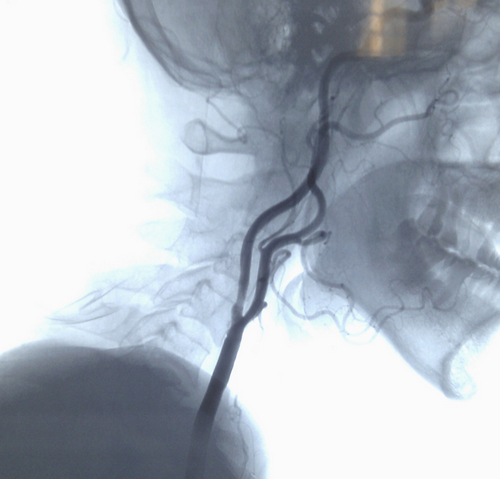

患者入院后行DSA 检查示右颈内动脉重度狭窄。2012年9月2日。张勤奕教授受邀于石家庄市中心医院为其施行了右侧颈内动脉内膜剥脱术,手术圆满成功。患者恢复良好。